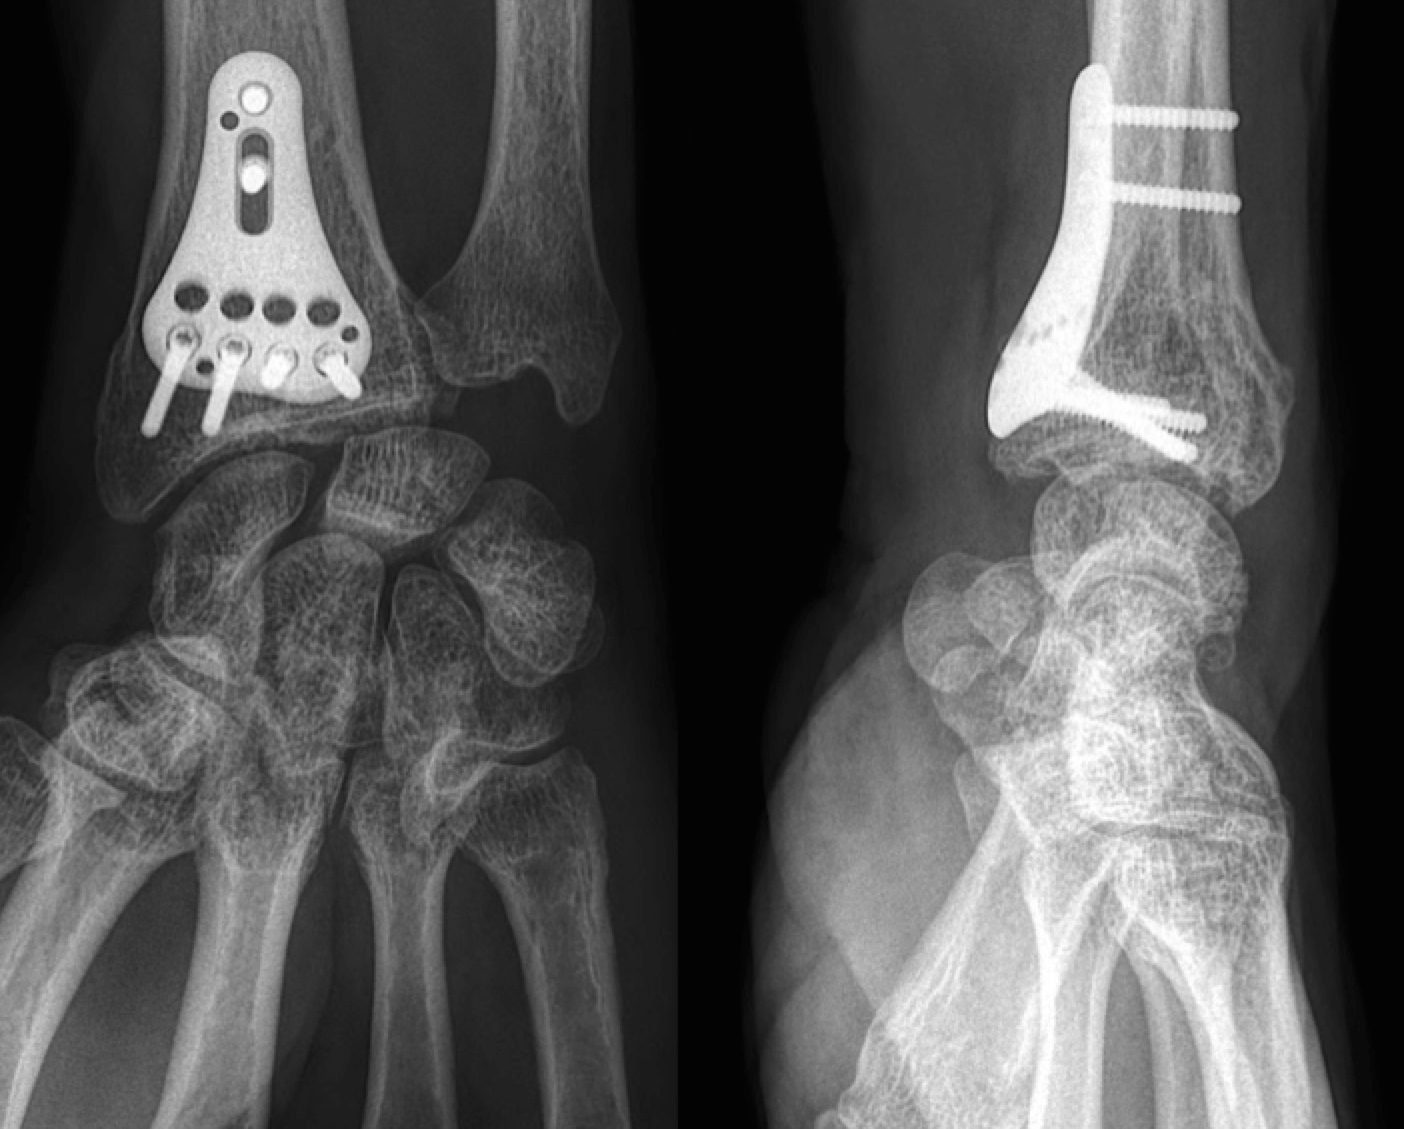

From centre-main-sud-loire.fr

Fracture du radius plaque palmaire Centre Main Sud Loire Lesion Plaque Palmaire Lésions de la plaque palmaire de l’interphalangienne proximale vues secondairement avec un flexum supérieur à 20. What are the characteristics of palmar. Palmarerythema is redness involving the heel of the palm, and occasionally the fingers. Lésions de la plaque palmaire. La plaque palmaire est avulsée en proximal et peut être interposée à la base de la première phalange, et la. Lesion Plaque Palmaire.